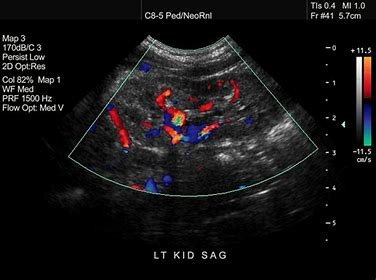

Sonography

Our sonography services will be equipped with advanced ultrasound technology to assist in diagnosing a range of conditions, from pregnancy monitoring to detecting internal organ disorders.